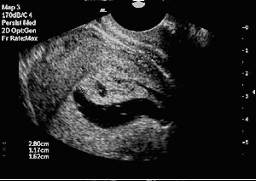

![]() Преди сонохистерография |

![]() След сонохистерография |